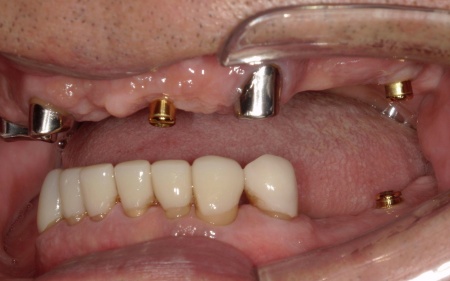

次に、上下左右の奥歯部に1本ずつ、左上前歯に1本、計5本のインプラントを埋入する手術を行いました。

根管治療が終了した上の歯には、オーバーデンチャーの支えとなる内冠(入れ歯を安定させるための土台)を、インプラント部分にはロケーター(義歯をしっかり固定するための連結装置)を装着しました。

この仕組みにより、必要に応じて入れ歯の取り外しを可能にしながら、日常生活では安定した状態を保つことができます。

次に上下顎に装着するため、チタン床を使用した金属床義歯を作製しました。

チタンは軽量でありながら強度が高く、体になじみやすい特徴をもつ素材です。また、金属床にすることで従来の樹脂製義歯と比べて薄く作ることが可能になり、装着による違和感の軽減も見込めます。

また、上顎は残存歯が少ないためすべてを覆う総入れ歯で、下顎は前歯がしっかり残っているため部分入れ歯の形で作製しました。